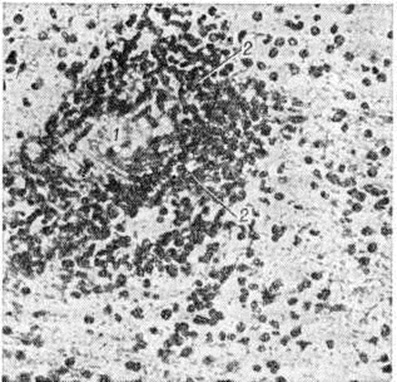

ЛейкоэнцефалитЛейкоэнцефалит (leukoencephalitis; греческий leukos белый + enkephalos головной мозг + itis) — воспалительно-дистрофическое поражение белого вещества головного мозга. Лейкоэнцефалит относятся к демиелинизирующим заболеваниям (смотри полный свод знаний). Впервые заболевание из группы Лейкоэнцефалит описал Дансон (J. Danson) в 1933 год под названием «подострая форма летаргического энцефалита». В 1939 год Петте и Деринг (Н. Pette, G. Doring) сообщили об энцефалите с хронический прогрессирующим течением, несколько отличающимся по клинические, и патоморфологический проявлениям, назвав его узелковым панэнцефалитом. В 1945 год это же заболевание описано Ван-Богартом (L. Van Bogaert) как «подострый склерозирующий лейкоэнцефалит». В дальнейшем Ван-Богарт тщательно изучил клинику и морфологию этой хронический прогрессирующей формы энцефалита. С группой Лейкоэнцефалит также сходны описанный в 1912 год Шильдером (P. F. Schilder) диффузный периаксиальный энцефалит и геморрагический Лейкоэнцефалит, о котором сообщил Херст (Е. W. Hurst)B 1941 год Этиология и патогенез. Предполагается, что Лейкоэнцефалит являются заболеваниями инфекционно-аллергической природы. Дискутируется роль миксовирусов, вирусов кори, бешенства и Herpes zoster как пусковых факторов гиперергического аутоиммунного процесса. Классификация. Выделяют следующие клинико-морфологический формы Лейкоэнцефалит: подострый склерозирующий лейкоэнцефалит Ван-Богарта, периаксиальный лейкоэнцефалит Шильдера, острый геморрагический Лейкоэнцефалит. При Лейкоэнцефалит демиелинизирующий процесс обычно сочетается с поражением нейронов в той или иной степени, поэтому для некоторых его форм употребляется также термин «панэнцефалит». Патологическая анатомия. Макроскопическое исследование мозга при Лейкоэнцефалит выявляет расширение борозд и атрофию извилин. На срезе полушарий определяются различного размера участки деструкции и демиелинизации во всех отделах мозга, преимущественно в белом веществе, но захватывающие различные участки серого вещества коры (рисунок 1). В наиболее поражённых отделах мозг имеет губчатую консистенцию, желудочки мозга умеренно расширены. Гистологический картина характеризуется диффузной подострой воспалительной реакцией с периваскулярной инфильтрацией лимфоцитами и плазмоцитами и очаговой демиелинизацией (рисунок 2). Воспалительные изменения преимущественно локализованы в белом веществе мозга, иногда в коре, подкорковых ганглиях, мозговых оболочках. Разрушается нормально сформированный миелин (миелинокластический тип поражения). Степень демиелинизации и деструкции нервной ткани варьирует в различных очагах. Отдельные мелкие очаги могут сливаться. У краёв очага демиелинизации олигодендроциты увеличены, содержат амфофильные включения, в более поражённых участках они полностью исчезают. Кроме того, встречается много больших причудливой формы астроцитов с гиперхроматическими многодольчатыми или несколькими ядрами. Аксоны остаются относительно сохранными на ранних стадиях процесса, позднее в них могут быть дистрофические изменения. Нейроны коры полушарий большого мозга могут содержать включения двух типов: сферические частицы диаметром 30—40 микрометров и продолговатые, или тубулярные, структуры несколько меньшего диаметра. Включения чаще встречаются при небольшой длительности заболевания. Гистохимический исследования обнаруживают во включениях большое количество белка. В большинстве случаев находят пролиферативную реакцию глии. Глиоз может быть мелкоузелковый или в виде крупных очагов (псевдоопухоль). Диффузное разрастание волокнистой глии приводит иногда к уплотнению мозгового вещества, так что мозг на разрезе имеет хрящевидную консистенцию. Стенки артерий и вен утолщены, с избытком ретикулярных волокон в адвентиции. Клиническая картина. Нервно-психические нарушения являются наиболее ранним проявлением заболевания. Вначале отмечаются жалобы на повышенную утомляемость, вялость, раздражительность, неустойчивость настроения. Постепенно круг нервно-психических расстройств расширяется. Появляется злобность, аффективность, жадность, эгоистичность, жестокость, недисциплинированность, инертность мышления. Больные часто совершают немотивированные поступки, теряют навыки опрятности. |